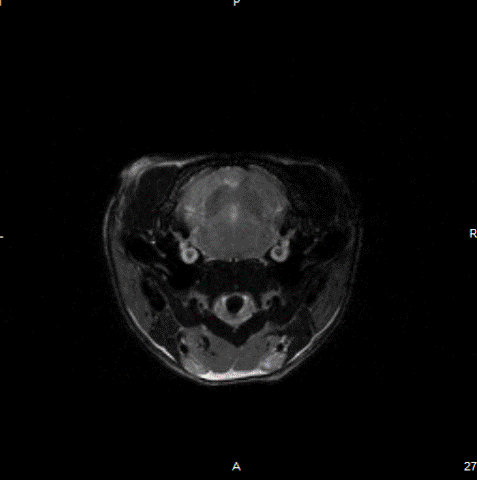

Epilepsy in the rat brain: T2- weighted images of a rat brain 48 hours after induction of epilepsy. Image Credit: Scintica Instrumentation Inc

T2- weighted images of a rat brain 48 hours after induction of epilepsy. Image Credit: Scintica Instrumentation Inc